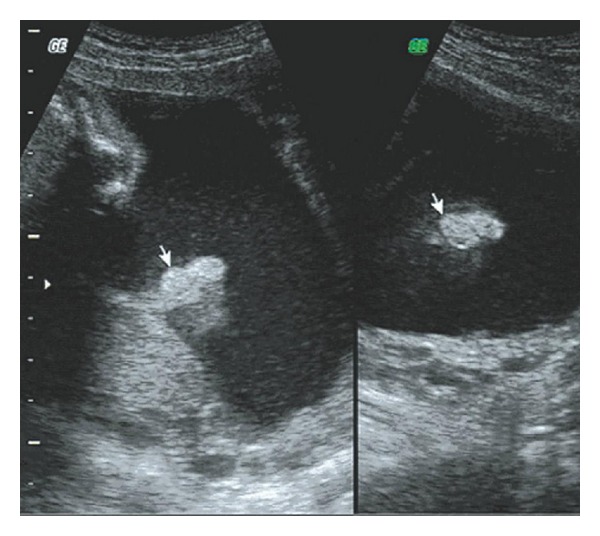

Five cases of anomalous ears were screened out in the examination and none of them were associated with deformities of other organs. Of these one had a small bilateral microtia with malformed external auditory canal (Figures 1 and 2) and one had unilateral auricle with abnormal morphology. The remaining three cases had unilateral microtia (Figures 3 and 4).

Figure 3.

Sonogram of unilateral microtia on auricular parasagittal section.